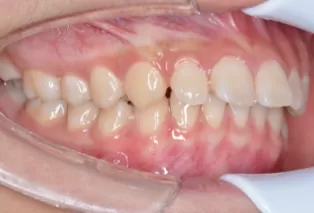

Photos intra-orales

teeth straightening aligners 4

teeth straightening aligners 5

teeth straightening aligners 6

teeth straightening aligners 7

teeth straightening aligners 8